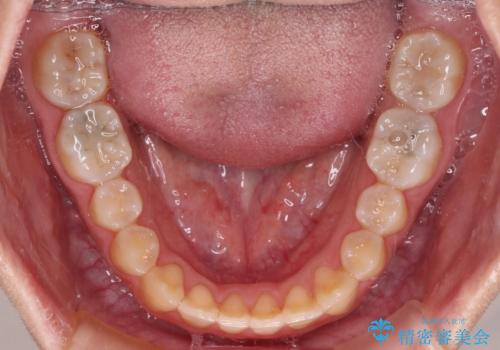

受け口で開咬を急速拡大装置とインビザラインで改善 欠損部分はインプラントにて補綴治療

- 前歯の開咬と、受け口による咬み合わせの悪さを気にして来院された患者様です。

左上は後続永久歯の欠損によりスペースがあり、矯正治療と並行してインプラントあるいはブリッジによる補綴治療が必要な状況でした。

上顎歯列が狭窄していたため、急速拡大装置により上顎骨を側方に拡大し、その後インビザラインにて矯正治療を行うこととしました。